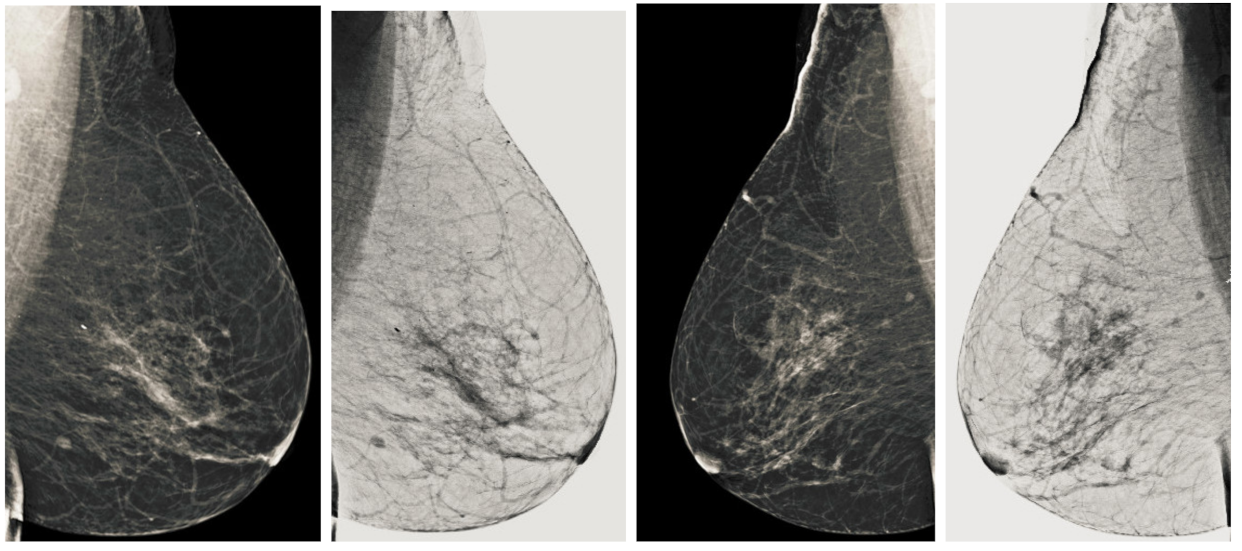

Figure 11.

Analysis of CC view of BI-RADS-3 mammogram images.

Figure 12.

Analysis of MLO view of BI-RADS-3 mammogram images.

We also measured the PSNR, the image contrast, and the EME of each category of databases, as we analyzed the image in terms of visual observation. The Table 3 shows the performance of our proposed image enhancement method. It can be seen from the Table 3 that our proposed method improved PSNR, contrast, and EME, and this also shows that our method can work on every category of BI-RADS. Because many techniques do not work on higher grade BI-RADS due to the complexity and the images are not of good quality. We obtained an average improvement in PSNR, contrast, and EME in the Table 4. For more observations, we analyzed the visual image of each category and we analyzed the CC and MLO of each category as shown in the Figure 7, Figure 8, Figure 9, Figure 10, Figure 11, Figure 12, Figure 13, Figure 14, Figure 15 and Figure 16. From the figures, every detail of image of every category can be observed, leading to better segmentation of the abnormal region. This image enhancement technique can be used as preprocessing steps for the detection of breast cancer. It is a very fast processing algorithm and it takes on 21.13 s. It gives opportunity to medical experts to analyze the mammogram images very quickly to propose the timely treatment.